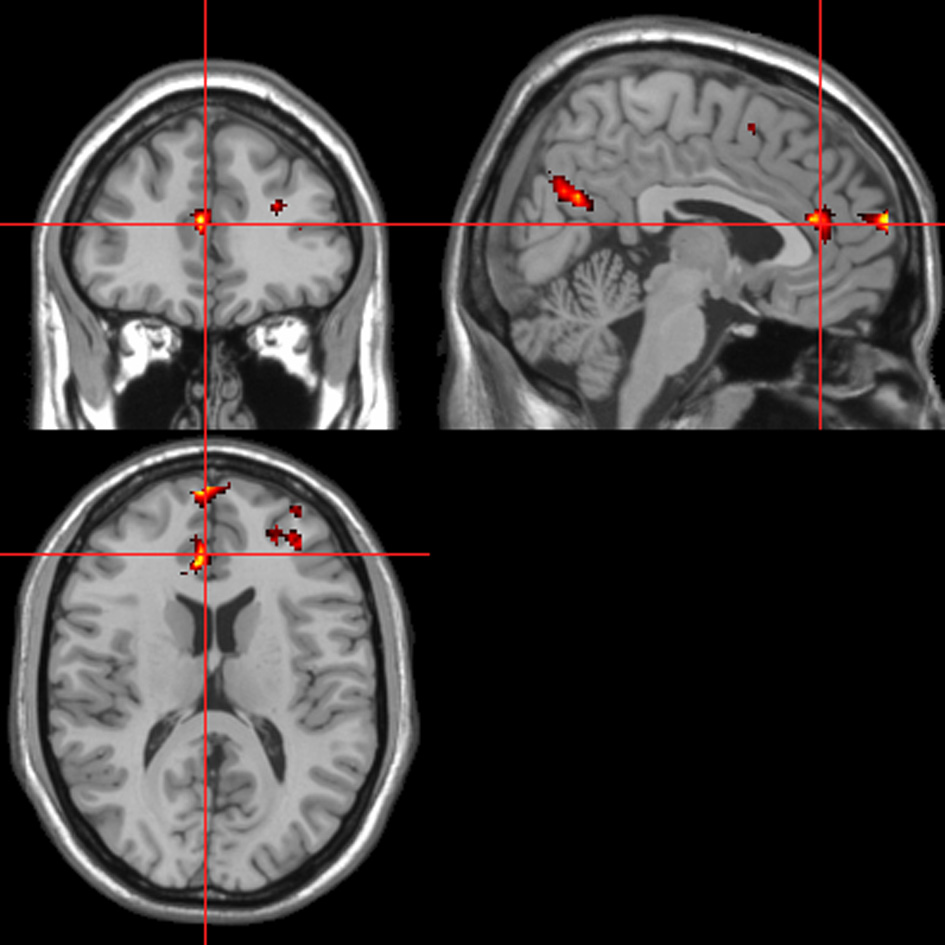

fMRI—behavioral response regressor

Across all stimuli, “threatening” compared with “harmless” behavioral assessments were associated with activation of bilateral middle frontal gyrus (MidFG; BA 10/46), mPFC/frontal pole (BA 10), anterior cingulate cortex (ACC; BA 24/32), precuneus (BA 7), and lingual gyrus (BA 18; Table 2; Figure 6). Threatening pictures were associated with activation including bilateral parahippocampal gyrus/lingual gyrus (BA 30/19), bilateral angular gyrus/temporo-parietal junction (BA 39), mPFC/ACC (BA 10/32), and posterior cingulate/precuneus (BA 31/7; Table 3A and Figure 7). This bilateral parahippocampal gyrus activation survived FWE correction at p < 0.05. Threatening sentences were associated with activation including bilateral MidFG/frontal pole (BA 10), bilateral ACC (BA 24), posterior cingulate and precuneus (BA 30/7; Table 4A and Figure 9). This left ACC activation survived FWE correction at p < 0.05. Threatening sounds were associated with activation including right transverse temporal gyrus (also known as Heschl's gyrus; BA 41) and bilateral middle/superior temporal gyrus (BA 21/22/42; Table 5A and Figure 11).

Figure 6

“Threatening” > “harmless” regressor across picture, sentence, and sound stimuli. Main effect of stimuli subjectively assessed as “threatening” across modalities. Flexible factorial design p < 0.001. Extent threshold = 10. See Table 2 for anatomical descriptions and co-ordinates.

Figure 7

Pictures. Activations associated with “threatening” compared with “harmless” behavioral responses. Flexible factorial design p < 0.001. Extent threshold = 10. See Table 3A for anatomical descriptions and co-ordinates.